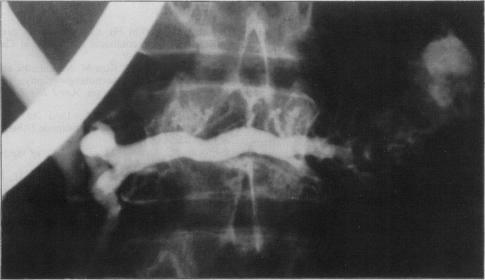

Pancreatography in chronic pancreatitis: international definitions.

Gut. 1984 Oct;25(10):1107-12. doi: 10.1136/gut.25.10.1107.